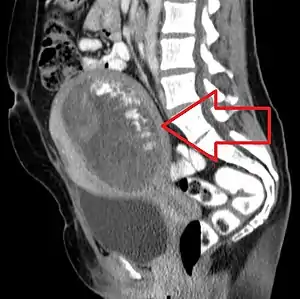

| Molar pregnancy seen on CT scan, sagittal view | |